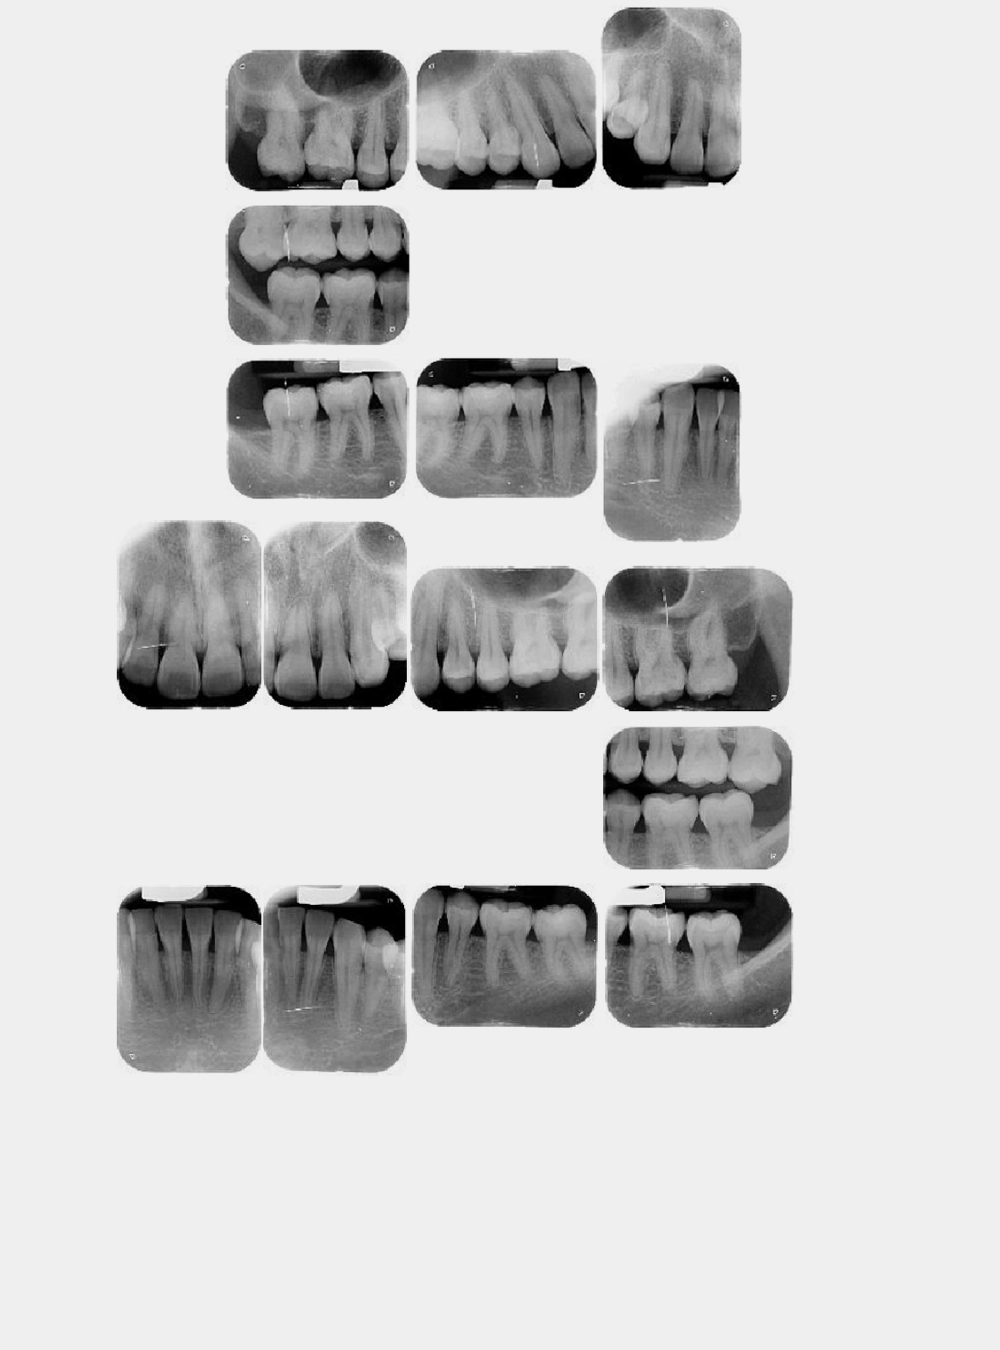

Rx Periapical Individual

Rx Serie Periapical Completa

Radiografías Intra Orales

• Periapical Individual

• Serie Periapical Completa